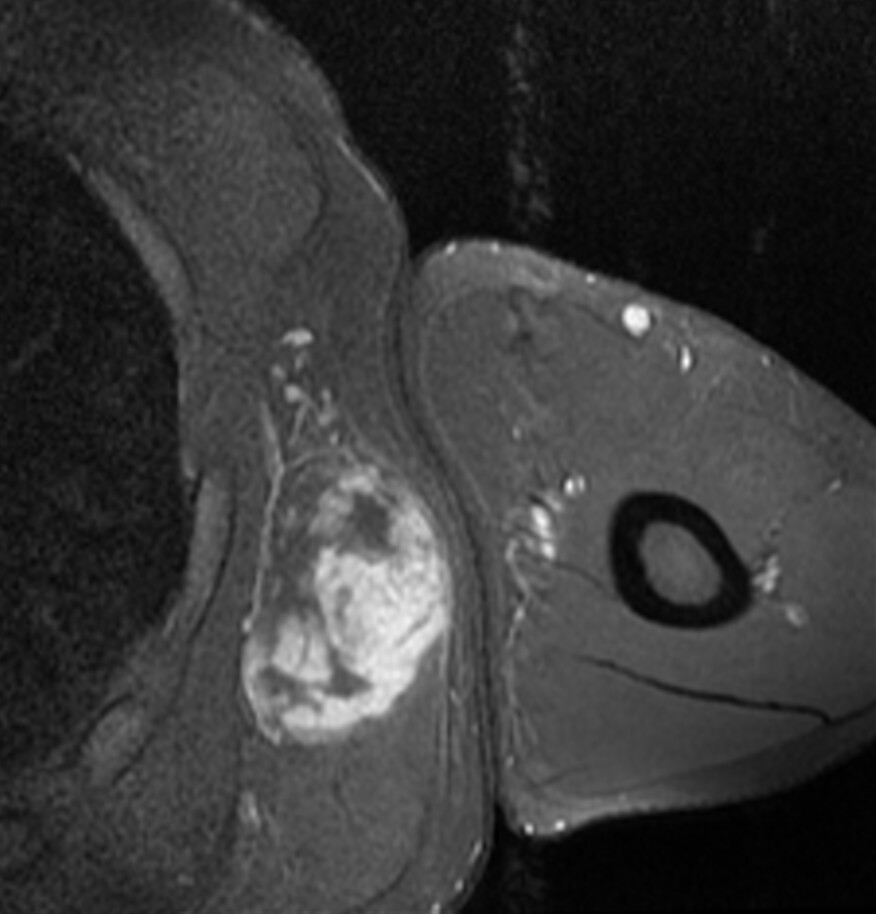

Фото Липосаркомы Мягких 114 фото